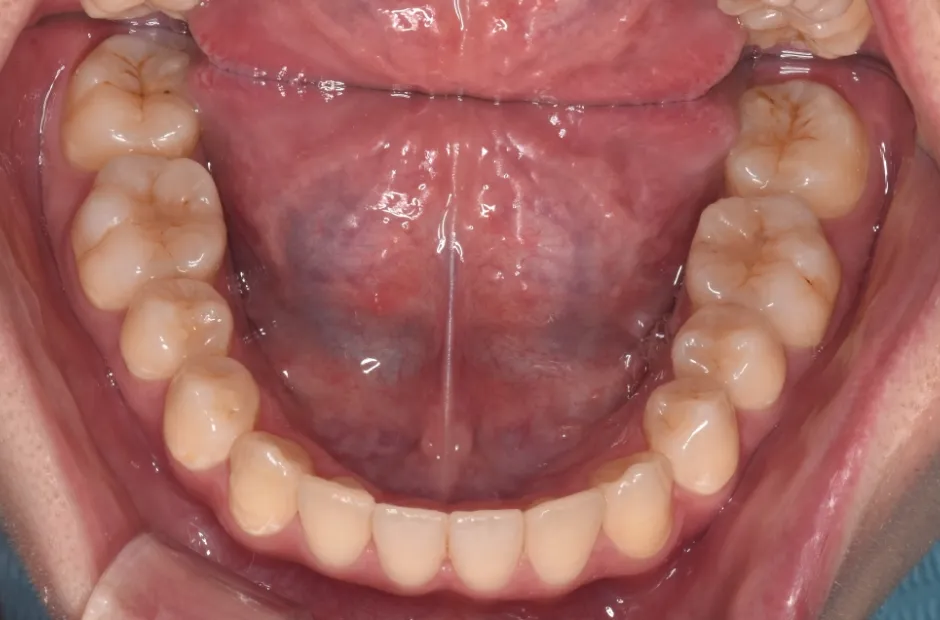

叢生

| 診断名・主訴 | 叢生 |

|---|---|

| 年齢・性別 | 43歳・女性 |

| 治療期間・回数 | 2年7か月 27回 |

| 治療に用いた主な装置 | 舌側矯正 |

| 抜歯部位 | 両顎4,4 |

| 治療費 | 100万円(税抜) |

| リスク・副作用 | 装置による違和感・疼痛・歯肉退縮・歯根吸収・虫歯のリスクなど |

治療後